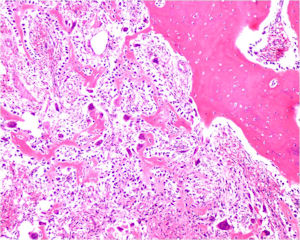

Osteosarcoma:

- Cellular atypia

- High mitotic rate

- Atypical mitotic figures

- Abundant lacelike osteoid

- Permeative growth into adjacent bone and soft tissue

- Presence of neoplastic cartilage

- No peripheral shell of reactive bone

- Osteoblastomas that are greater than 4 cm and that show prominent periosteal new bone formation may present problems in differentiation from osteosarcoma

- May have foci of lace-like osteoid, high cellularity and more than a few scattered mitotic figures but these characteristics usually occur independently in an osteoblastoma vs all these atypical characteristics being present in an osteosarcoma